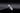

Имплант Straumann BLT 4.1*8mm SLActive - установлен в субкрестальное положение, произведено профилирование кортикальной кости системой Straumann Bone Profiler с целью создания более выгодного профиля прорезывания и исключения костной резорбции в области шейки импланта.

Чтобы компенсировать недостаточный объем мягких тканей проведена - мягкотканая пластика деэпителизированным соединительнотканным трансплантантом с неба.

Установлен заживляющий абатмент диаметром 6.5 мм.

Обратите внимание на объем и качество мягких тканей в области будущей финальной реставрации!